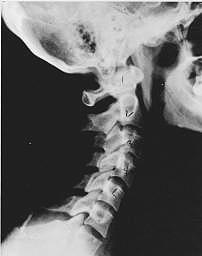

This is a side x-ray view of the neck. As with all the pictures you will see on this page, the patient is looking to the right of the screen, so you are viewing the right side of their neck. We will call this picture a "near normal" spine. Compare this spine with the ones you will see below on this page. Notice the normal forward curve of the neck. This curve helps absorb shock. Notice how each of the disc spaces between C2 (second bone in neck) and C7 are thick and even, this again is normal. Also notice how the front portions (right on the x-ray) of each of the vertebrae (called the 'body' of the vertebrae) are fairly square with clear and well defined borders. This type of arrangement is normal in the neck. Normal vertebrae in other parts of the spine also have similar characteristics to what we see here. When subluxations occur and are left uncorrected, ongoing relentless changes occur that result in damage to the structure and function of the spine along with nerve damage and the resulting problems caused from improper nerve supply.